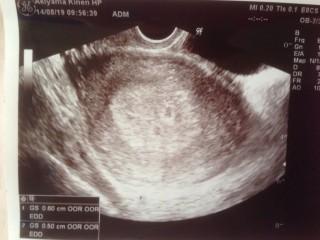

初めて受診しました。 胎嚢を確認出来て、「ちゃんと妊娠していますね」と言われました。 すごく嬉しかったです。 胎嚢の大きさは0.84cmでした。 次の受診は2週間後です。 心拍確認出来るといいな!